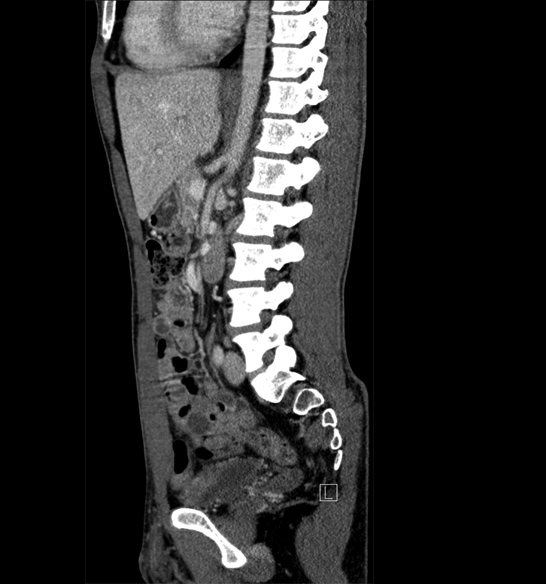

Body

Covers abdominal CT anatomy.